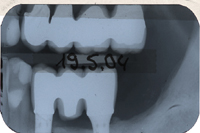

Das Röntgenbild von Abb. 5 zeigt die absolut perfekte knöcherne Situation der Unterkieferimplantatbrücke zwei Jahre nach der Zementierung.